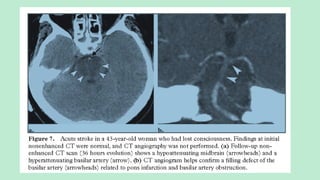

NECT scans: Dense basilar artery sign.

Hypodensity in the occipital lobes and/or

thalami may be apparent.

MRI: Depending on thrombus extent and

vascular supply to the distal PCAs.

T2/FLAIR hyperintensity and diffusion

restriction in the midbrain, thalami, upper

pons, and superior cerebellar hemispheres

are common.